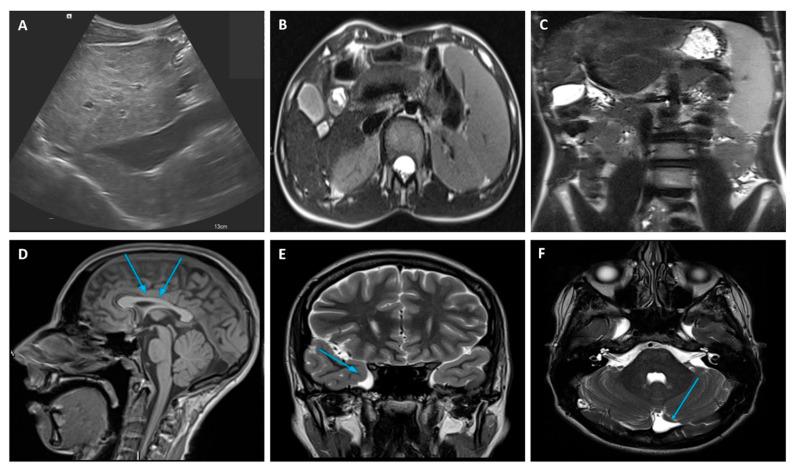

Zhu-Tokita-Takenouchi-Kim (ZTTK) syndrome, an intellectual disability syndrome first described in 2016, is caused by heterozygous loss-of-function variants in . Haploinsufficiency in may affect multiple genes, including those involved in the development and metabolism of multiple organs. Considering the broad spectrum of functions, it is to be expected that pathogenic variants in this gene can cause a wide spectrum of clinical symptoms. We present an additional ZTTK syndrome case due to a de novo heterozygous variant in the gene (). The clinical manifestations of our patient were similar to those present in previously reported cases; however, the diagnosis of ZTTK syndrome was delayed for a long time and was carried out during the diagnostic work-up of significant chronic liver disease (CLD). CLD has not yet been reported in any series; therefore, our report provides new information on this rare condition and suggests the expansion of the ZTTK syndrome phenotype, including possible liver involvement. Correspondingly, we recommend screening patients with variants specifically for liver involvement from the first years of life. Once the CLD has been diagnosed, an appropriate follow-up is mandatory, especially considering the role of as an emerging player in cancer development. Further studies are needed to investigate the role of haploinsufficiency as a downregulator of essential genes, thus potentially impairing the normal development and/or functions of multiple organs.

Zhu-Tokita-Takenouchi-Kim (ZTTK) 综合征是一种智力障碍综合征,于 2016 年首次描述,由 上的杂合功能丧失变异引起。 可能会影响多个基因的单倍不足,包括涉及多个器官发育和代谢的基因。考虑到 广泛的功能,预计该基因中的致病性变异可引起广泛的临床症状。我们报告了另一个由于 基因()上的新生杂合变异引起的 ZTTK 综合征病例()。我们患者的临床表现与以前报道的病例相似;然而,ZTTK 综合征的诊断被延迟了很长时间,并且是在对显著慢性肝病(CLD)进行诊断性检查期间进行的。在任何系列中均未报告过 CLD;因此,我们的报告提供了有关这种罕见情况的新信息,并提示 ZTTK 综合征表型的扩展,包括可能的肝脏受累。相应地,我们建议从生命的最初几年开始,对携带 变异的患者进行肝脏受累的特异性筛查。一旦诊断出 CLD,就必须进行适当的随访,尤其是考虑到 作为癌症发展中新兴参与者的作用。需要进一步的研究来探讨 单倍不足作为必需基因下调因子的作用,从而可能损害多个器官的正常发育和/或功能。